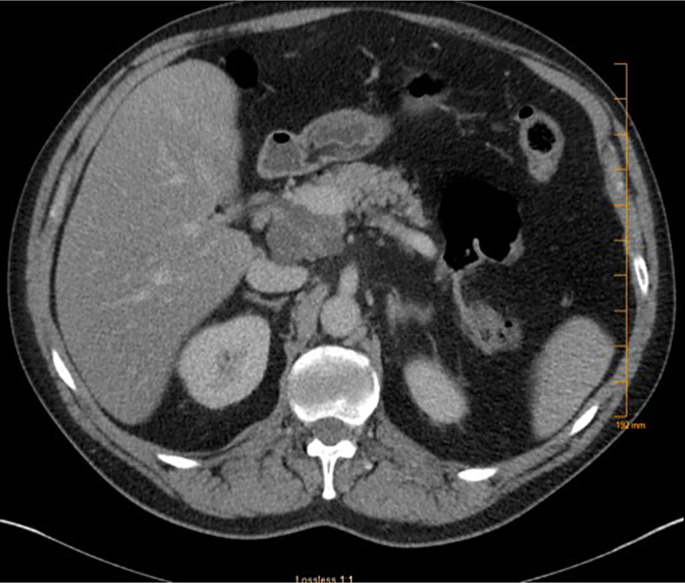

Case presentation: A 60-year-old female with an unremarkable medical history presented with epigastric pain for 2 weeks. Her initial laboratory workup was notable for mild isolated elevation of alkaline phosphatase. Abdominal computed tomography revealed a 5.0 × 4.0 cm cystic lesion in the pancreatic head with thick internal septations. Magnetic resonance cholangiopancreatography showed a 5.2 × 4.5 × 6.8 cm lobulated cystic lesion in the pancreatic head with a microcystic configuration, multiple internal septations, and a hypointense central scar. Endosonographic examination showed a large multicystic lesion in the pancreatic head region. Fine-needle aspiration showed a carcinoembryonic antigen level of 555 ng/mL and an amylase level of 13,593 U/L. No KRAS or GNAS mutations or loss of heterozygosity was detected. Subsequently, the patient underwent a Whipple procedure. Pathologic examination revealed a complex cystic lesion with well-differentiated acinar cells and patches of ductal epithelium compatible with ACC. Histological examination confirmed the presence of low-grade PanIN without invasive carcinoma. The patient recovered well from surgery, and repeat imaging 2 months later was unremarkable.